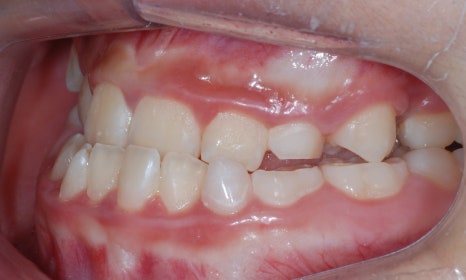

우리가 흔히 주걱턱이라고 하는 제3급 부정교합(Class III malocclusion)의 경우 위턱이 발달하지 못하던가 아래턱이 위턱보다 많이 발달하기 때문에 흔히 앞니 부위의 반대교합 양상이 나타나게 됩니다.

반대교합이란 위 앞니가 아래 앞니를 덮지 못하고 아래 앞니가 더 앞으로 나와 물리는 교합 형태를 말합니다. 이러한 반대교합은 부모님들이 비교적 알아채기 쉬우며, 발견되는 즉시 치료를 해주는 것이 필요합니다.

반대교합 (crossbite)

절단교합 (edge bite)

그러나 제3급 부정교합이지만 반대교합이 아닌 위아래 앞니가 끝끼리 부딪히는 절단교합의 경우에는 부정교합의 문제점을 알아채기 쉽지 않습니다. 이렇게 앞니끼리 부딪히게 되면 앞니에도 과도한 힘이 가해져서 앞니 치아의 뿌리가 짧아질 수 있으며, 잇몸뼈가 내려가거나 잇몸 퇴축이 일어날 수 있습니다.

본 환자는 만 10세 남환으로 소아치과에서 부정교합으로 진단받고 치료를 위해 내원하셨습니다. 정밀검사 결과 제3급 부정교합을으로 송곳니와 어금니는 3급 교합관계를 보이고 있었습니다. 앞니의 반대교합이 심하고 아래턱이 현저하게 많이 발달했을 경우에는 위턱뼈의 확장과 성장교정을 먼저 시행하는 것이 필요합니다.